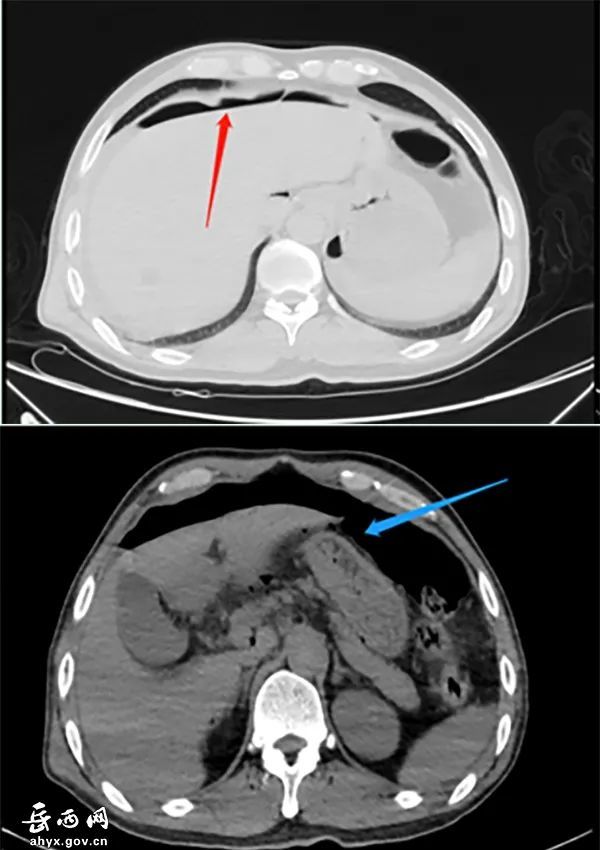

治疗期间出现腹痛难忍,行上腹部ct检查提示:胃窦部穿孔,急诊行胃穿孔

图片尺寸2048x1394